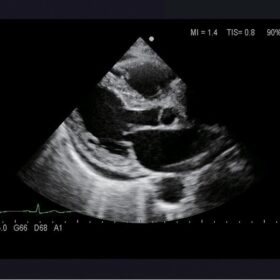

Ultrasound Aloka Prosound Alpha 6 – Image Gallery and Videos

Cardiovascular

ProSound 6 offers a full complement of various analyzing software. Dual Dynamic Display (D.D.D.), Free Angular M-mode (FAM), and Doppler Auto Trace make daily examinations more comfortable. Software such as Asynchrony Study, Tissue Doppler Imaging (TDI), Strain, eTRACKING provide more detailed, quantitative evaluation. The ProSound 6 is ready for the fundamentals and more.